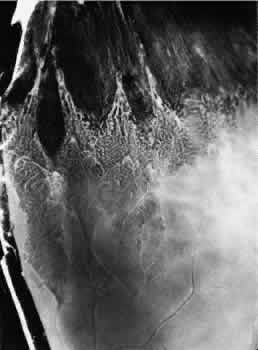

TYPICAL CYSTOID DEGENERATION

The most common form of degeneration of the peripheral retina is typical cystoid degeneration. Spaces develop in the outer plexiform and inner nuclear layers and coalesce to form interlacing tunnels; they are separated by pillars that extend from the inner to the outer retinal layers, giving the inner surface a uniformly stippled appearance (Fig. 15). The stippled depressions correspond to retinal pillars; the intervening rounded domes result from the intraretinal cystoid spaces.9 Degeneration begins at the ora serrata, particularly at the base of dentate processes, and extends posteriorly and circumferentially to form a band that may encircle the eye and reach from the ora serrata to the equator (Fig. 16).

Fig. 16. Typical and reticular cystoid degeneration found immediately behind the ora serrata and about enclosed ora bay near cut edge of calotte. Posteriorly, note the conspicuous vascular pattern of degeneration (seen as gray background), finely stippled surface pattern, and angular free margins (related to limitation by surface vessels).